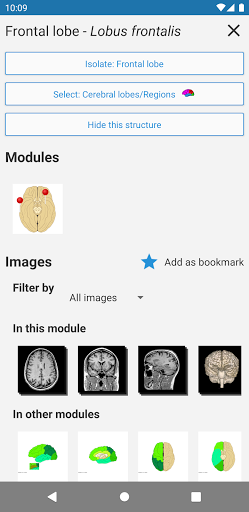

*Peningkatan tampilan detail bagian anatomi untuk memudahkan identifikasi dalam gambar modul saat ini dan modul lainnya.

-Dalam tampilan detail struktur anatomi , pin sekarang menunjukkan struktur terkait di semua gambar yang ada

Juga ketuk langsung pada gambar untuk menavigasi ke gambar yang disajikan dalam modul itu

- "Filter oleh", dalam tampilan detail Anda sekarang dapat menyaring gambar yang mengandung struktur anatomi oleh modalitas